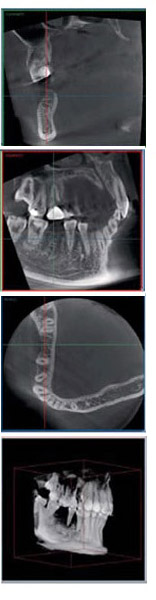

最新の歯科用CTを導入

PLANMECA ProMAX 2D 3D,プロマックス,3D,パノラマ,セファロアーム型X線CT診断装置

最新の歯科用CT 「PLANMECA ProMax 2D/3D」を導入しました。 高精密な3D画像を活用することで、安全・確実で高度な歯科治療をご提供できます。当院で導入している歯科用デジタルレントゲンCTは、患者さまの健康のため、診査診断に必要な被爆量が少なく、 一般医療用CT撮影の1/50~1/1010分の1程度まで被爆量を軽減することができます。 また、当院で導入している歯科用デジタルレントゲンCTは、従来のX線写真と違い立体的にお口の中の状態を把握することができ、今までは見えないものが見える、わからなかった部分がわかるようになり、「安全・確実・安心」の治療に結びつきます。実はCT撮影で最も重要なのは、機種そのものではなく、撮影した画像を画面表示するコンピュータソフトウェアです。当院で導入したCTは、口腔内の状態の縦・横・正面の3方向だけでなく、斜めからのスライス断面まで、さまざまな表現で表示することができるロメキシス3Dイメージングソフトウェアを搭載しています。画像再構成の精度も高く、実際の顎に限りなく近い立体画像を表示することができますので、より診断価値の高い3D画像を得られ、正確で歪みのない3D画像を得ることが可能ですので、治療の再に正確な診断が行えます。